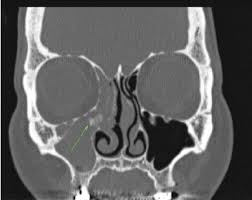

Pdf Effects Of Surgery And Topical Medication On Eosinophilic Granulomatosis With Polyangiitis With Otitis Media And Sinusitis A Case Report

Pdf Effects Of Surgery And Topical Medication On Eosinophilic Granulomatosis With Polyangiitis With Otitis Media And Sinusitis A Case Report from www.researchgate.net

However, it's possible — and even somewhat more likely — to have chronic sinusitis. (b, c) polyps in the middle nasal meatus on the left side and in the olfactory cleft on the right side can be seen. Or is it exacerbated by the use of my cpap at night? Medication to treat nasal polyps and chronic sinusitis. But most were dislodged after 14 weeks. Your healthcare provider will take a health history and do a physical exam. No one knows exactly why some people get nasal polyps. Small nasal polyps may not cause symptoms. To remove any nasal polyps, your ent physician uses a small nasal telescope, and lances the polyp. Surgery, such as functional endoscopic sinus surgery (fess), may be. Nasal polyps are noncancerous growths caused by long term swelling inside of your nose. Mometasone nasal spray 200 mcg once or twice daily is appropriate to reduce symptoms and it may decrease the size of nasal polyps in patients who have chronic rhinosinusitis. They result from chronic inflammation due to asthma, recurring infection, allergies, drug sensitivity, or.